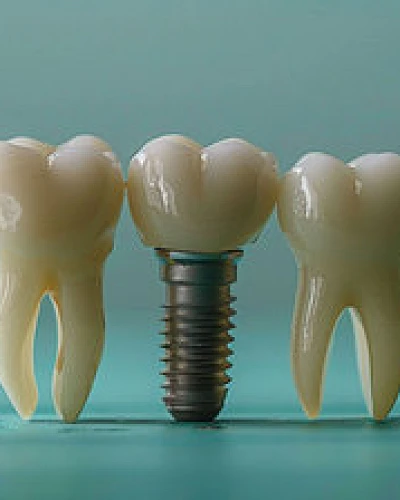

Implantes Dentales

Recupere la base de su sonrisa con nuestros implantes dentales de primera calidad. Utilizamos planificación digital avanzada y cirugía guiada por ordenador para colocar postes de titanio o zirconio biocompatibles que actúan como raíces artificiales. Este procedimiento previene la pérdida ósea y proporciona una base estable y permanente para coronas a medida, devolviendo el 100% de la función masticatoria y la estética natural.